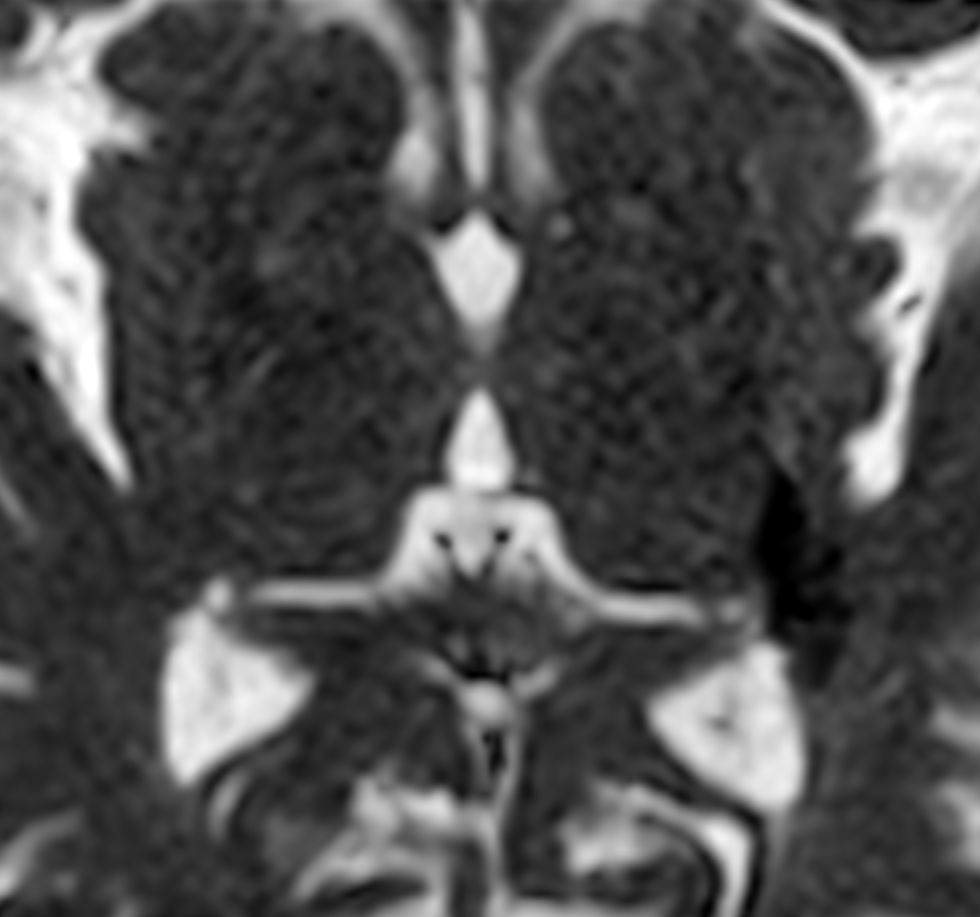

Zoom Diffusion (ADC)

-